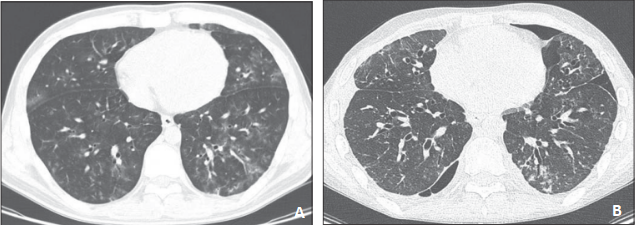

图1 52岁的女性植入综合征

图4 45岁男性急性髓系白血病患者

注:在allo-HSCT术后6个月后出现呼吸困难。A. 胸部CT显示支气管周围磨玻璃样改变;B. 1个月的随访CT显示疾病进展,磨玻璃样改变的范围增加、新进展的网格影及铺路石影、明显牵拉性支气管扩张[22]。